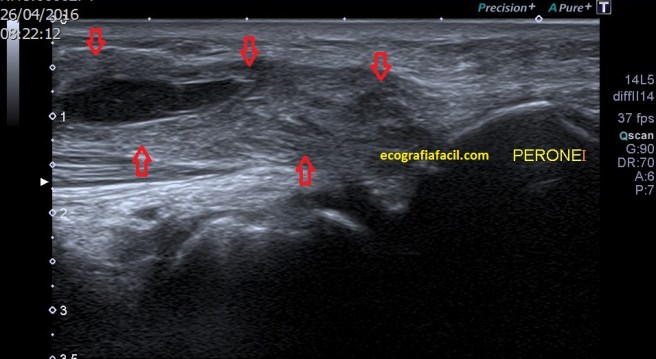

La inserción del Bíceps Femoral es diferente, lo hace, tanto su porción larga, como su porción corta, unidas, en la cabeza del Peroné, por tanto lateral. Mira:

Normalidad

Esta es una imagen, conseguida con un corte longitudinal, en situación normal…mira la misma imagen en una situación de rotura del Tendón del Bíceps Femoral:

Patología

En la imagen patológica que ves arriba es vital la localización del Peroné. Ahora te voy a pedir que compares y que observes como en la imagen de normalidad vemos un tendón hiperecogénico, marcado por flechas amarillas, homogéneo insertando en el Peroné…en la imagen siguiente el tendón está aumentado de tamaño, heterogéneo y con componente líquido, lo marcan las líneas rojas…Es precioso, ¿verdad?…ambas imágenes son de deportistas, una corredora y amiga, la imagen de normalidad y un futbolista, la imagen patológica.